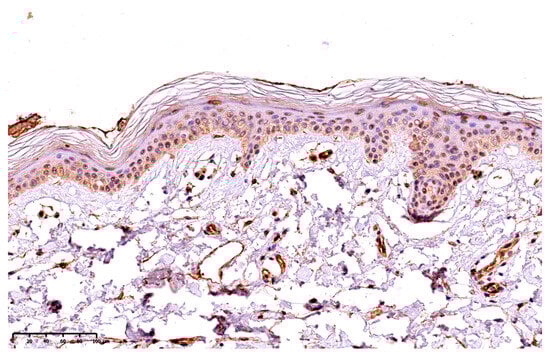

3.2. Tissue